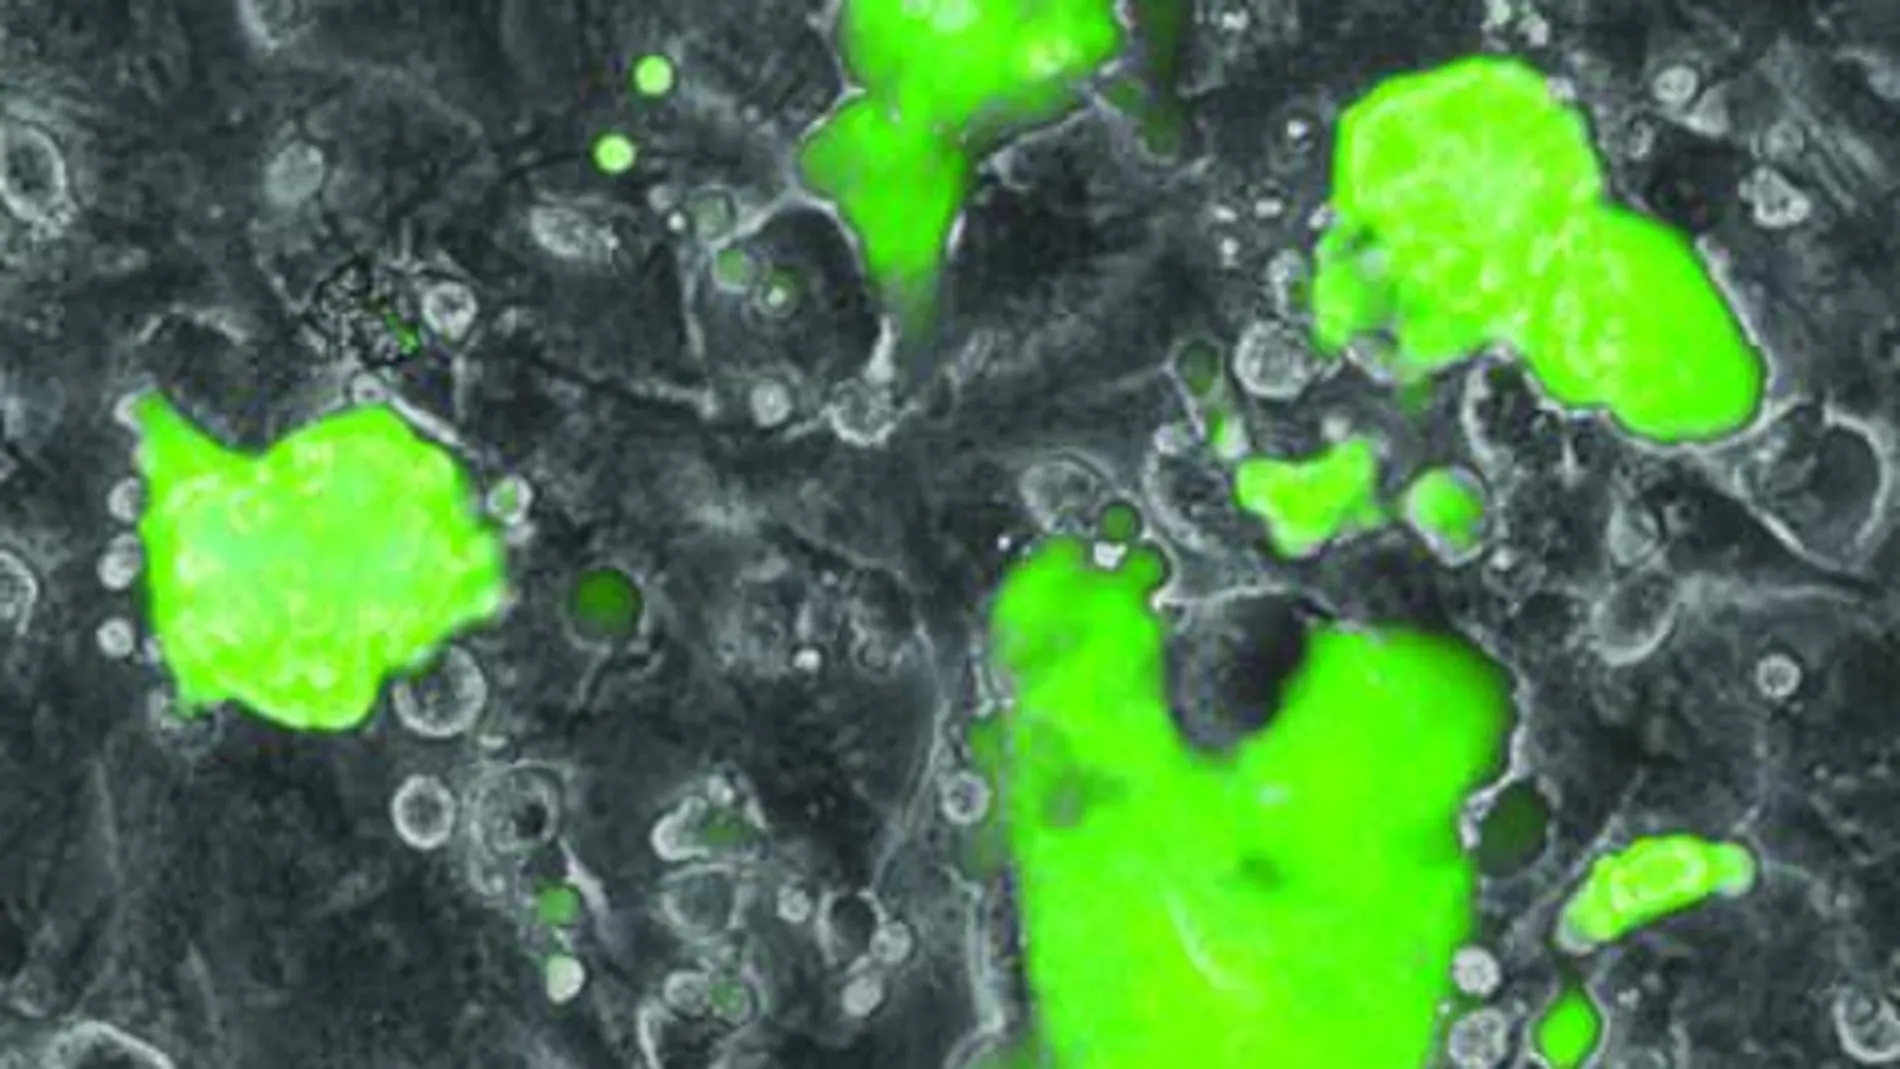

Un grupo de investigadores del Centro de Regulación Genómica en Barcelona descubren un mecanismo por el cual la reprogramación de células adultas a células madre pluripotentes inducidas (iPS) es mucho más rápida y eficiente.

Investigadores del Centro de Regulación Genómica (CRG) en Barcelona ahora describen un novedoso mecanismo por el que las células adultas consiguen reprogramarse en células iPS de forma competente y en un periodo muy corto. "En nuestro grupo utilizábamos un factor de transcripción concreto (C/EBPa) para reprogramar células de la sangre en otro tipo de célula sanguínea (transdiferenciación). Ahora hemos visto que este factor también actúa como catalizador a la hora de reprogramar células adultas en iPS", explica Thomas Graf, jefe de grupo en el CRG y profesor de investigación ICREA. "El trabajo que acabamos de publicar presenta una descripción detallada del mecanismo de reprogramación de una célula sanguínea a iPS. Ahora entendemos la mecánica que utiliza la célula para que podamos reprogramarla y conseguir que vuelva a ser pluripotente de forma controlada, con éxito y en un periodo corto de tiempo", añade Graf.

La información genética se encuentra compactada en el núcleo como una madeja de lana y, para acceder a los genes, debemos deshacer la madeja en la región que contiene la información que buscamos. Lo que consigue el factor C/EBPa es abrir temporalmente la región que contiene los genes responsables de la pluripotencia. De este modo, al iniciar el proceso de reprogramación, ya no hay lugar para el azar y los genes implicados están listos para ser activados y permitir la reprogramación en todas las células con éxito.

"Sabíamos que C/EBPa estaba relacionado con los procesos de transdiferenciación celular. Ahora sabemos cuál es su papel y por qué sirve de catalizador en la reprogramación"comenta Bruno Di Stefano, estudiante de doctorado en el laboratorio de Thomas Graf y primer autor del trabajo. "Siguiendo el proceso que describió Yamanaka, la reprogramación tardaba semanas, tenía una tasa de éxito muy pequeña y, además, acumulaba mutaciones y errores. Si incorporamos el factor C/EBPa, el mismo proceso se lleva a cabo en pocos días, con una tasa de éxito muy superior y con menos posibilidad de errores"afirma el joven científico.